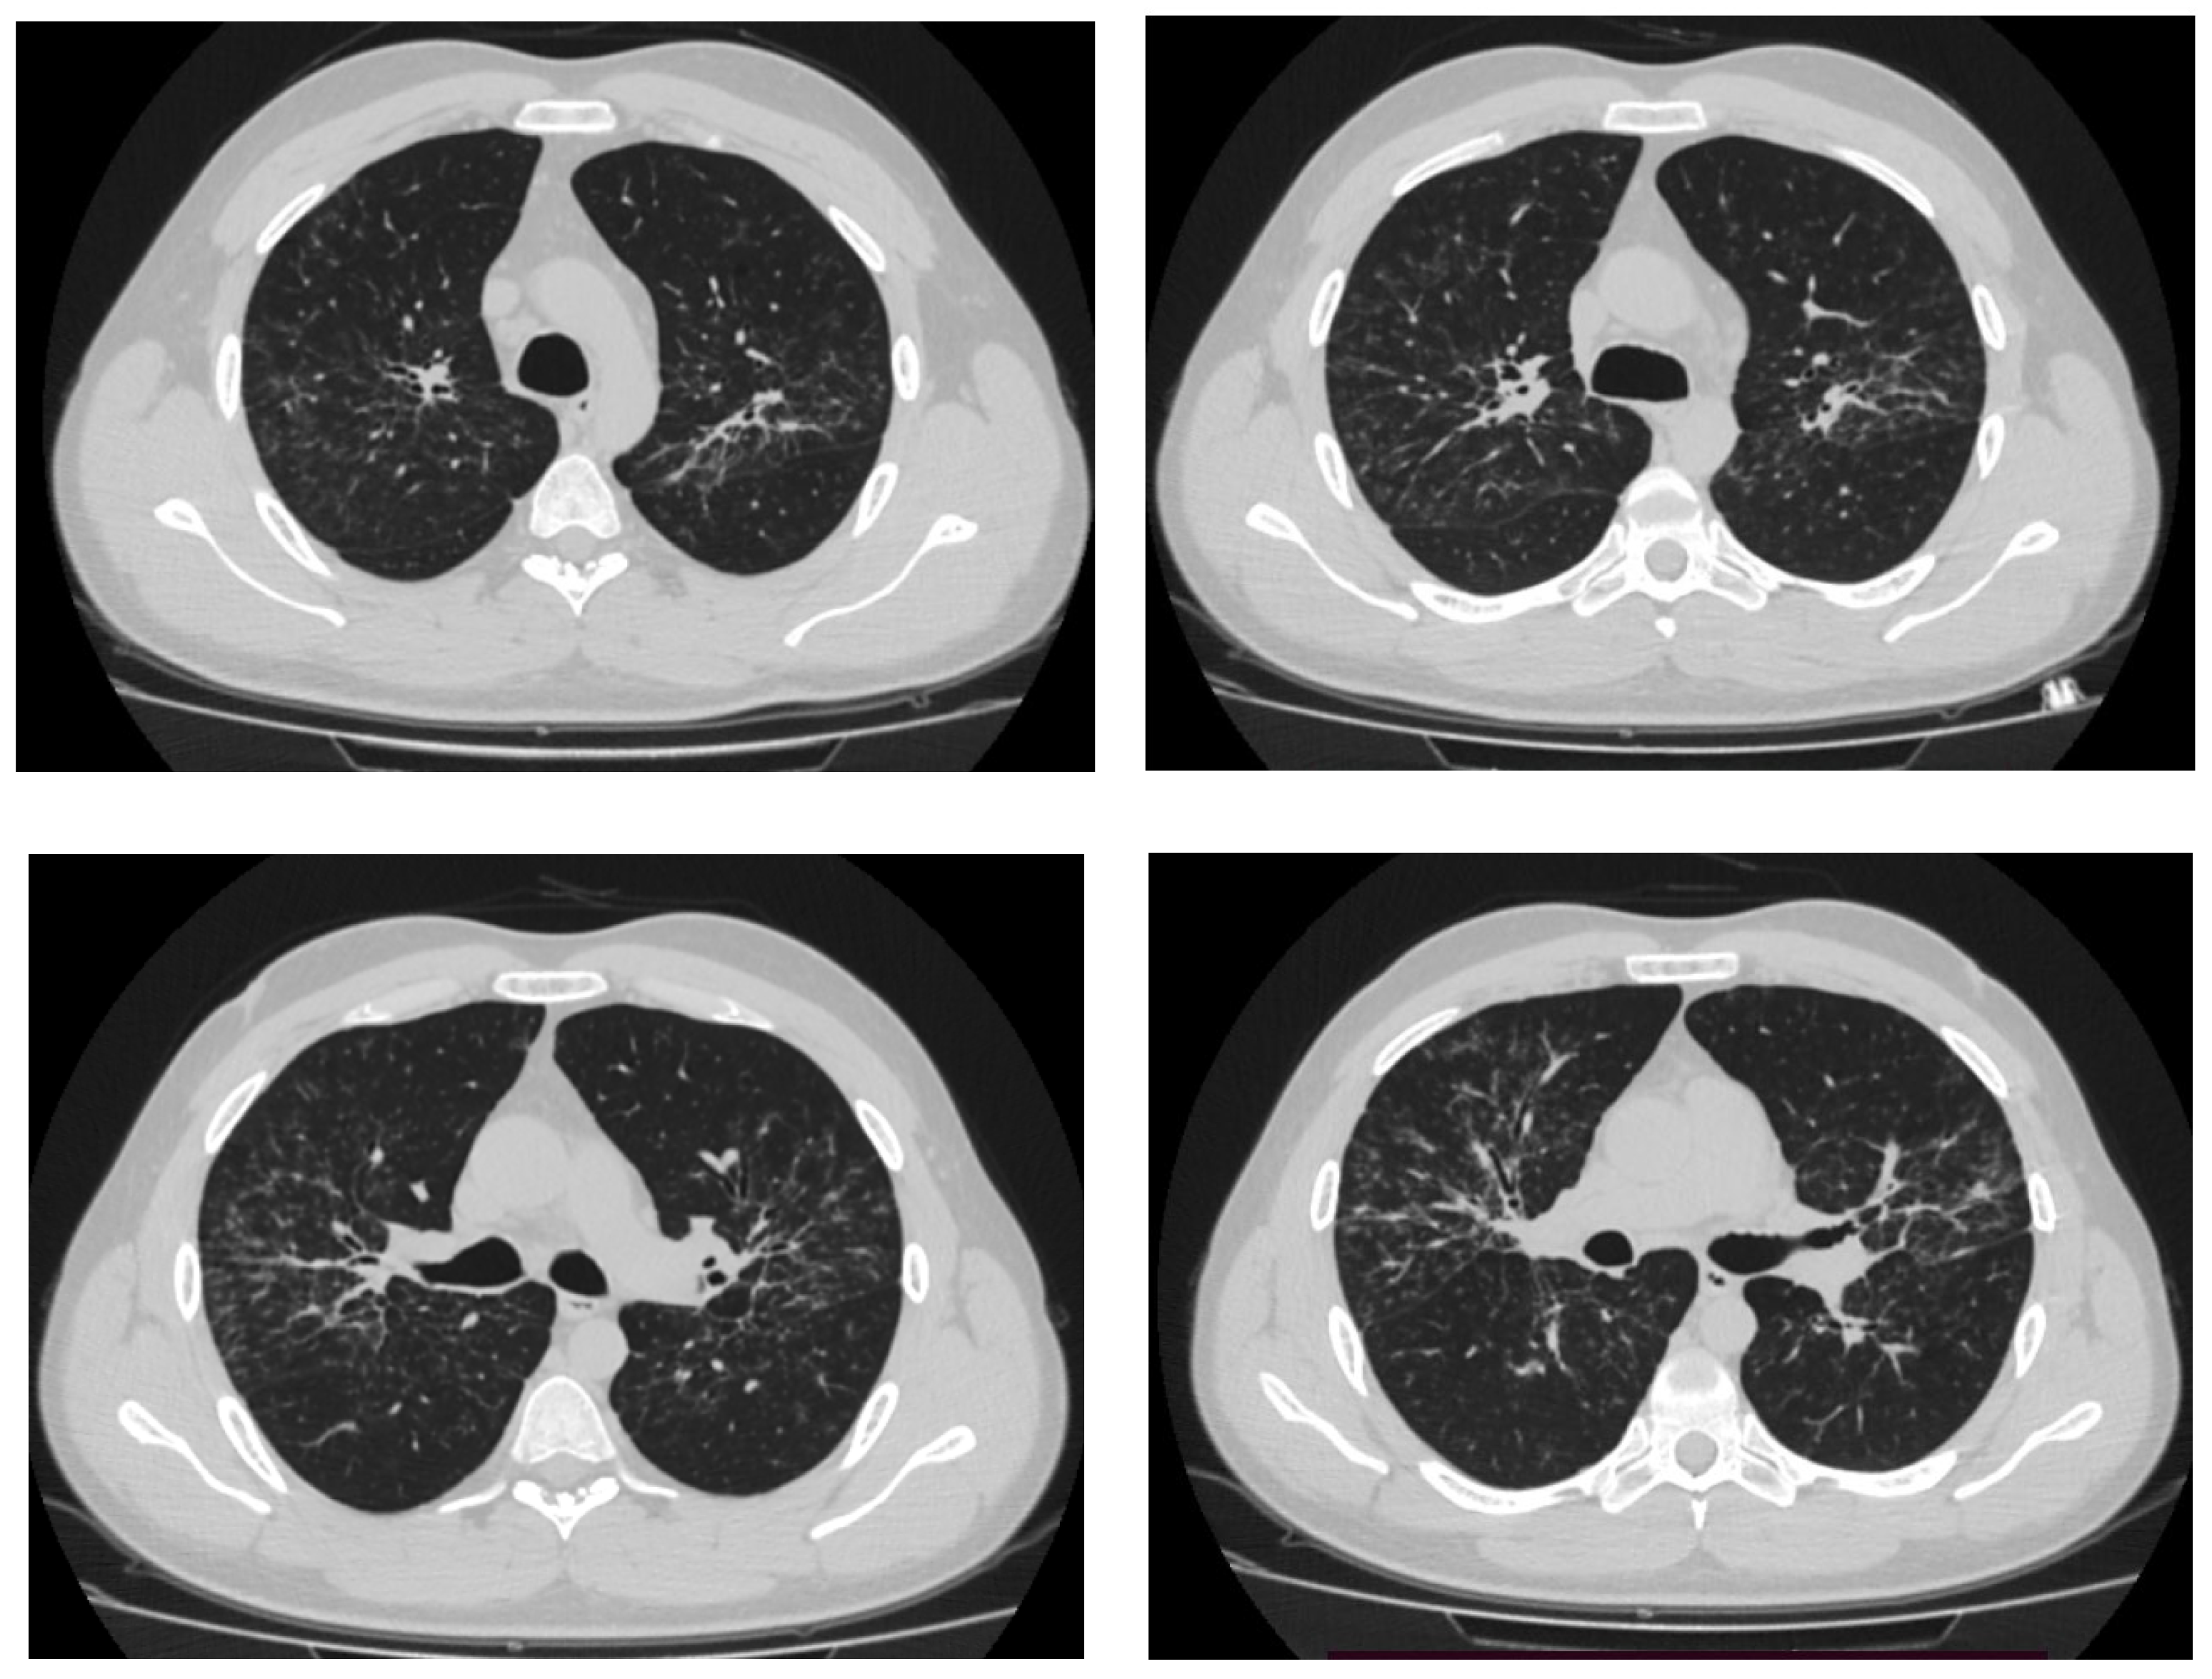

According to the results of CT of the chest organs, expansion of the mediastinum and lung roots on both sides due to enlargement of lymph nodes was detected, and numerous foci and foci on the background of the enhanced pulmonary pattern with bullous swellings were detected in all lung sections (Figure 1). Then he was examined in the City TB Dispensary: T-SPOT (negative), fibrobronchoscopy with flushes, and transbronchial lung biopsy were performed. M. tuberculosis DNA was not detected in the flushes, and cultures were negative. Biopsy results revealed epithelioid granulomas without necrosis. The patient was referred to the sarcoidosis office of the City Hospital.

Figure 1.

The results of MSCT of the chest organs.

The patient was further hospitalized in a city hospital. CT of the chest from 17.09.2019 revealed polygonal foci with irregular contours along the bronchovascular bundles in the pericissural parts of the lung fields, merging into large infiltrates, corresponding to the picture of stage II sarcoidosis. The increase in intrathoracic lymph nodes became more pronounced: paratracheal and tracheobronchial up to 33 × 30 mm, to the left of the aortic arch and aortic window up to 24 × 15 mm, bifurcation up to 34 × 32 × 17 mm, bronchopulmonary on both sides up to 25 mm in the largest diameter, and supraclavicular up to 9 mm in the largest diameter. Fluid in the pleural cavities was not determined.